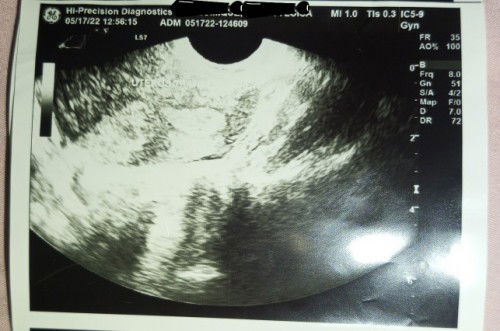

Alam n'yo ba basahin 'to mga mommy? Hindi ba s'ya buntis? Transverse view ng uterus n'ya ito #pleasehelp #advicepls